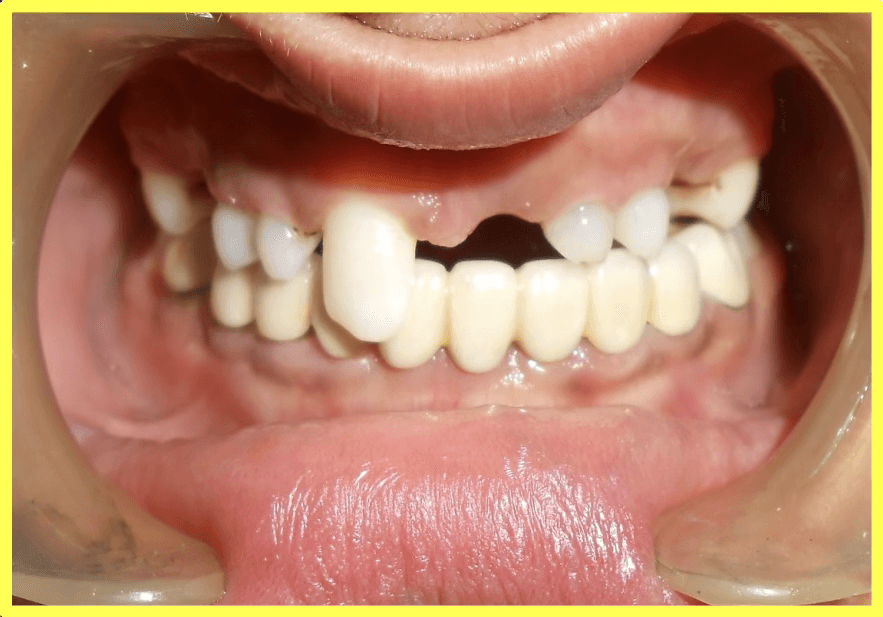

Final result

Upper and lower telescopic removable metallic PFM prosthesis was carefully fitted, adjusted, and delivered to restore complete dental function and aesthetics.